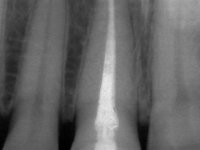

Female patient, 33 years old, non-smoker. Tooth 11 with endodontic treatment rehabilitated with a crown. This crown shows an infiltrated cervical interface. The smile line was high, this area being very visible. The patient had a thick gingival phenotype and good oral hygiene.

A pre-print was performed to make a crown in dual-cured resin. After a cross-section with a turbine, the infiltrated crown was removed with a microluxador. The dental stump was re-prepared to better define the shape and location of the cervical margin. It was necessary to place composite resin on the buccal surface of the provisional crown to improve its esthetics. The impression was made using a double-mix technique with two-viscosity, quick-setting silicones. In the laboratory, a crown with a ceramic-coated Zr infrastructure was made. After placing it in the mouth, we verified that the crown showed a greater translucency than the symmetrical one, not fulfilling our aesthetic goals. The ceramist had the opportunity to observe the situation in the clinic, collecting records for later rectification. The new crown was placed in the mouth and approved by the patient. The final cementation was done with resin-reinforced glass ionomer cement.